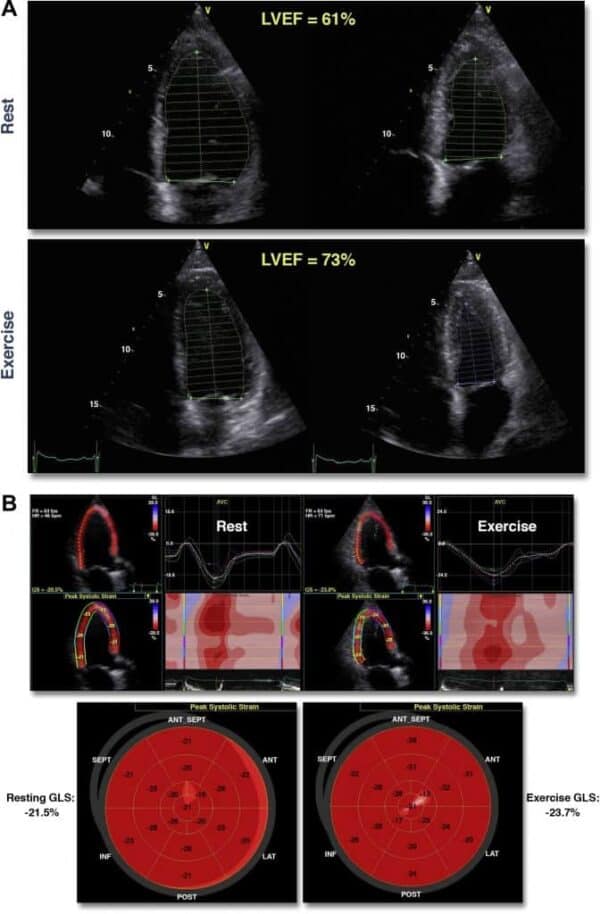

- Sirve para determinar la Fracción de eyección del ventrículo izquierdo con el WMSI

- El cardiólogo va a realizar imágenes de su corazón en reposo con el ecocardiograma

- Una vez que usted tenga la taquicardia. El cardiólogo tomara unas imágenes de su corazón durante el esfuerzo máximo